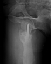

Пациент 63 года мужчина, остеосинтез чрезвертельного перелома проксимальным бедренным стержнем в октябре 2012. Постепенно появились и усилилиь боли в т.б.с., рентгенограммы показывают прорезание шеечного винта.

PDF, 131 Kb | Рентгенограммы до, после, через 2 мес и сейчас в приложении. Возможные варинаты: 1) реостеосинтез гамма-стержнем (но в наличии только 135-градусные, есть сомнения относительно фиксации винта в головке - вроде бы по первичным винт был установлен корректно, следовательно там сейчас полость); 2) реостеосинтез 95-клинковой пластиной. Просьба поделиться мнениями относительно возможных сложностей, за и против, может быть будут и другие варианты?

Винт был введен недостаточно глубоко, и главное - длина бедра не была полностью восстановлена.

Реостеосинтез проксимальным гвоздем тут проблематичен, надо исхитриться сделать то, что не сделали при первичном остеосинтезе, т.е. вальгусную репозицию, восстановить длину бедра, и винт ввести не в имеющийся канал, а кпереди, и буквально субхондрально.